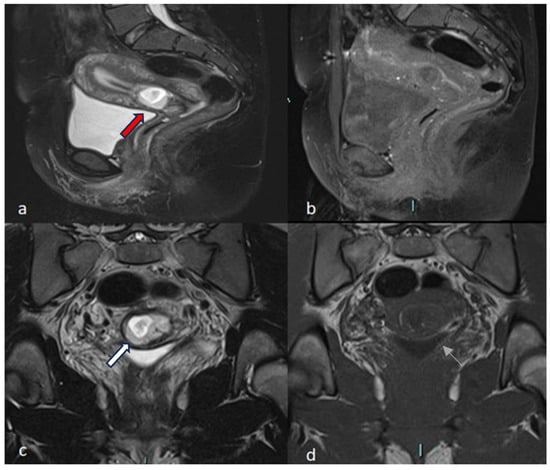

4.1.1. Case 1 (CSP Type I)

4.1.2. Case 2 (CSP Type II)

4.1.3. Case 3 (Low-Implanted Pregnancy)